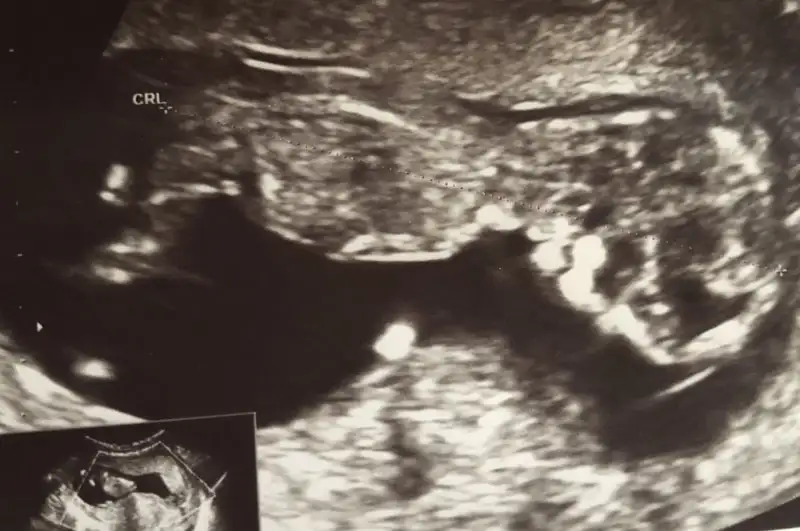

- 9 Nisan 2015

- 2.390

- 3.486

- 83

- 39